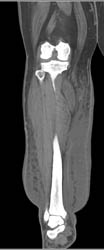

Diagnosis

Repeated Trauma to Elbow